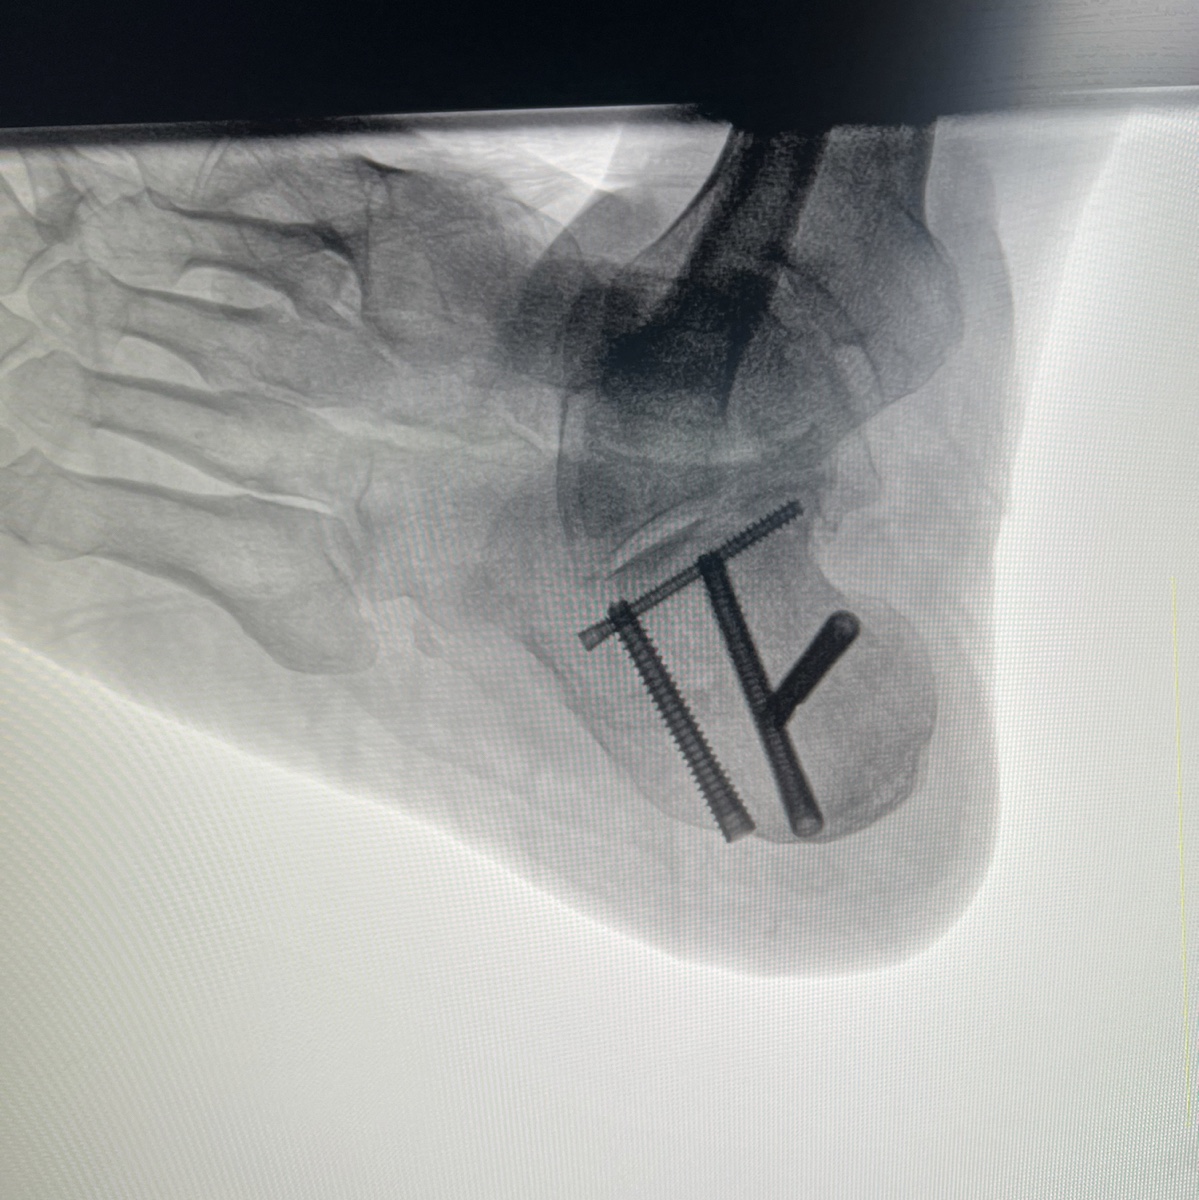

病例跟骨骨折(sanders IV)微创手术

【治疗经过及结果】:入院后行手术治疗

分享一例骨折病例